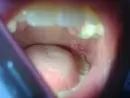

Пару дней назад у меня во рту появилась язвочка. Сначала она была небольшая, теперь немного увеличилась. Больно кушать и зевать. Стараюсь не есть горячее, острое и кислое, так же сухую твёрдую пищу. Пользуюсь мазью "Дентамет", наношу ее на ранку ватной палочкой, но в течение 4-х дней она только немного увеличилась.

Может, я делаю что-то не так? Что посоветуете?

Скорее всего, это прорезывается восьмой зуб.

В некоторых случаях, прорезывание "зуба мудрости" осложняется воспалением, вследствие чего формируется над коронкой зуба капюшон. Его рекомендуется иссечь, что обеспечит купирование воспалительного процесса, а также облегчит прорезывание зуба.

Для дифференциальной диагностики можно сделать рентгеновский снимок.